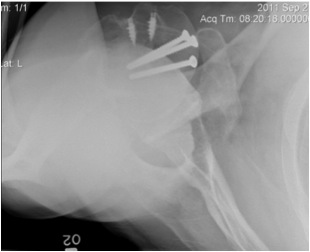

AP Xray

Abnormal overlap of humeral head on glenoid

Light-bulb sign - globular head secondary to internal rotation of the humeral head

Vacant Glenoid Cavity - > 6 mm space between humeral head and anterior rim of glenoid

Lesser tuberosity fractures

Displaced lesser tuberosity fractures